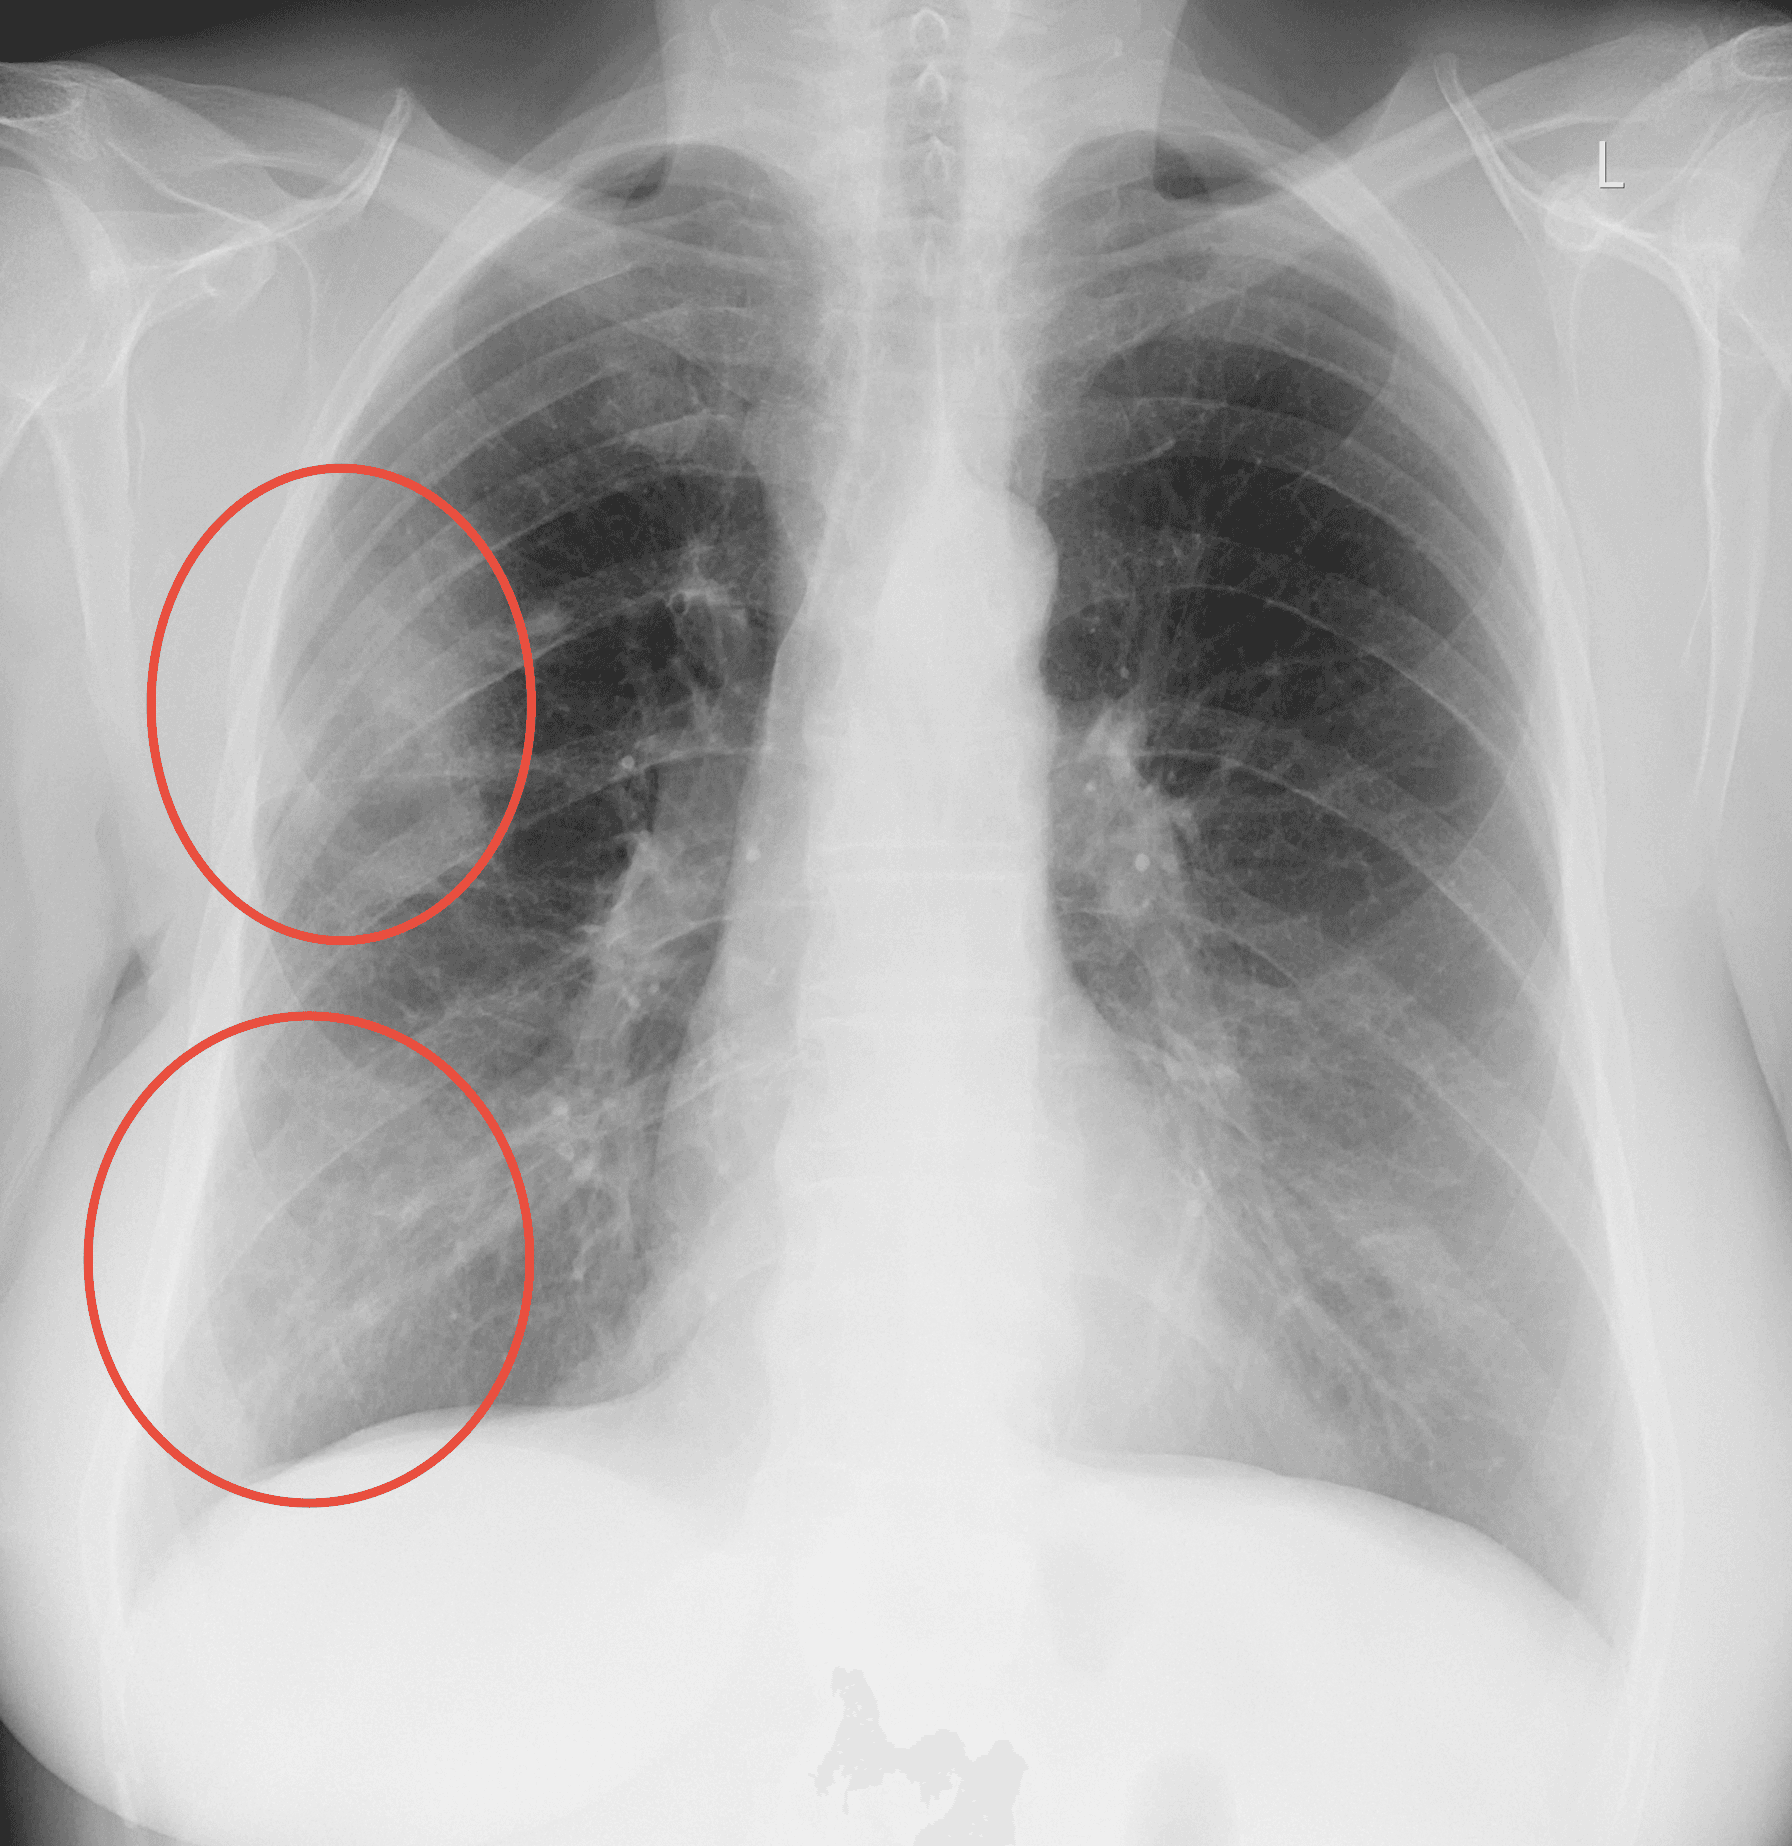

Medusa detected Emphysema in the lungs

98% certainty